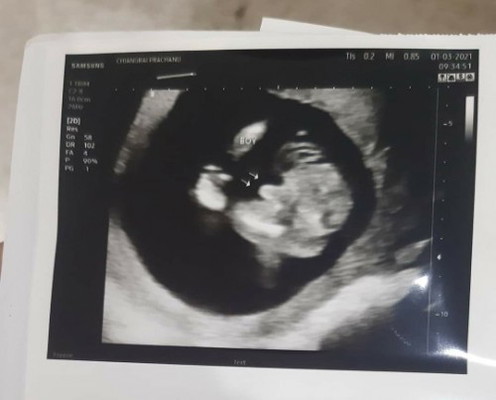

ขอสอบถามหน่อยค่ะ แม่ๆว่ามีโอกาสเป็นผู้หญิงได้ไหมคะ พอดีไปซาวอีกรอบหมอบอกน้องหนีบขาเหมือนผู้หญิง

เริ่มจะสับสนแล้วค่ะทั้งๆที่ใบซาวด์ก่อนหน้าชัดขนาดนี้😂😂

จู๋ชัดๆค่ะแม่😅😅